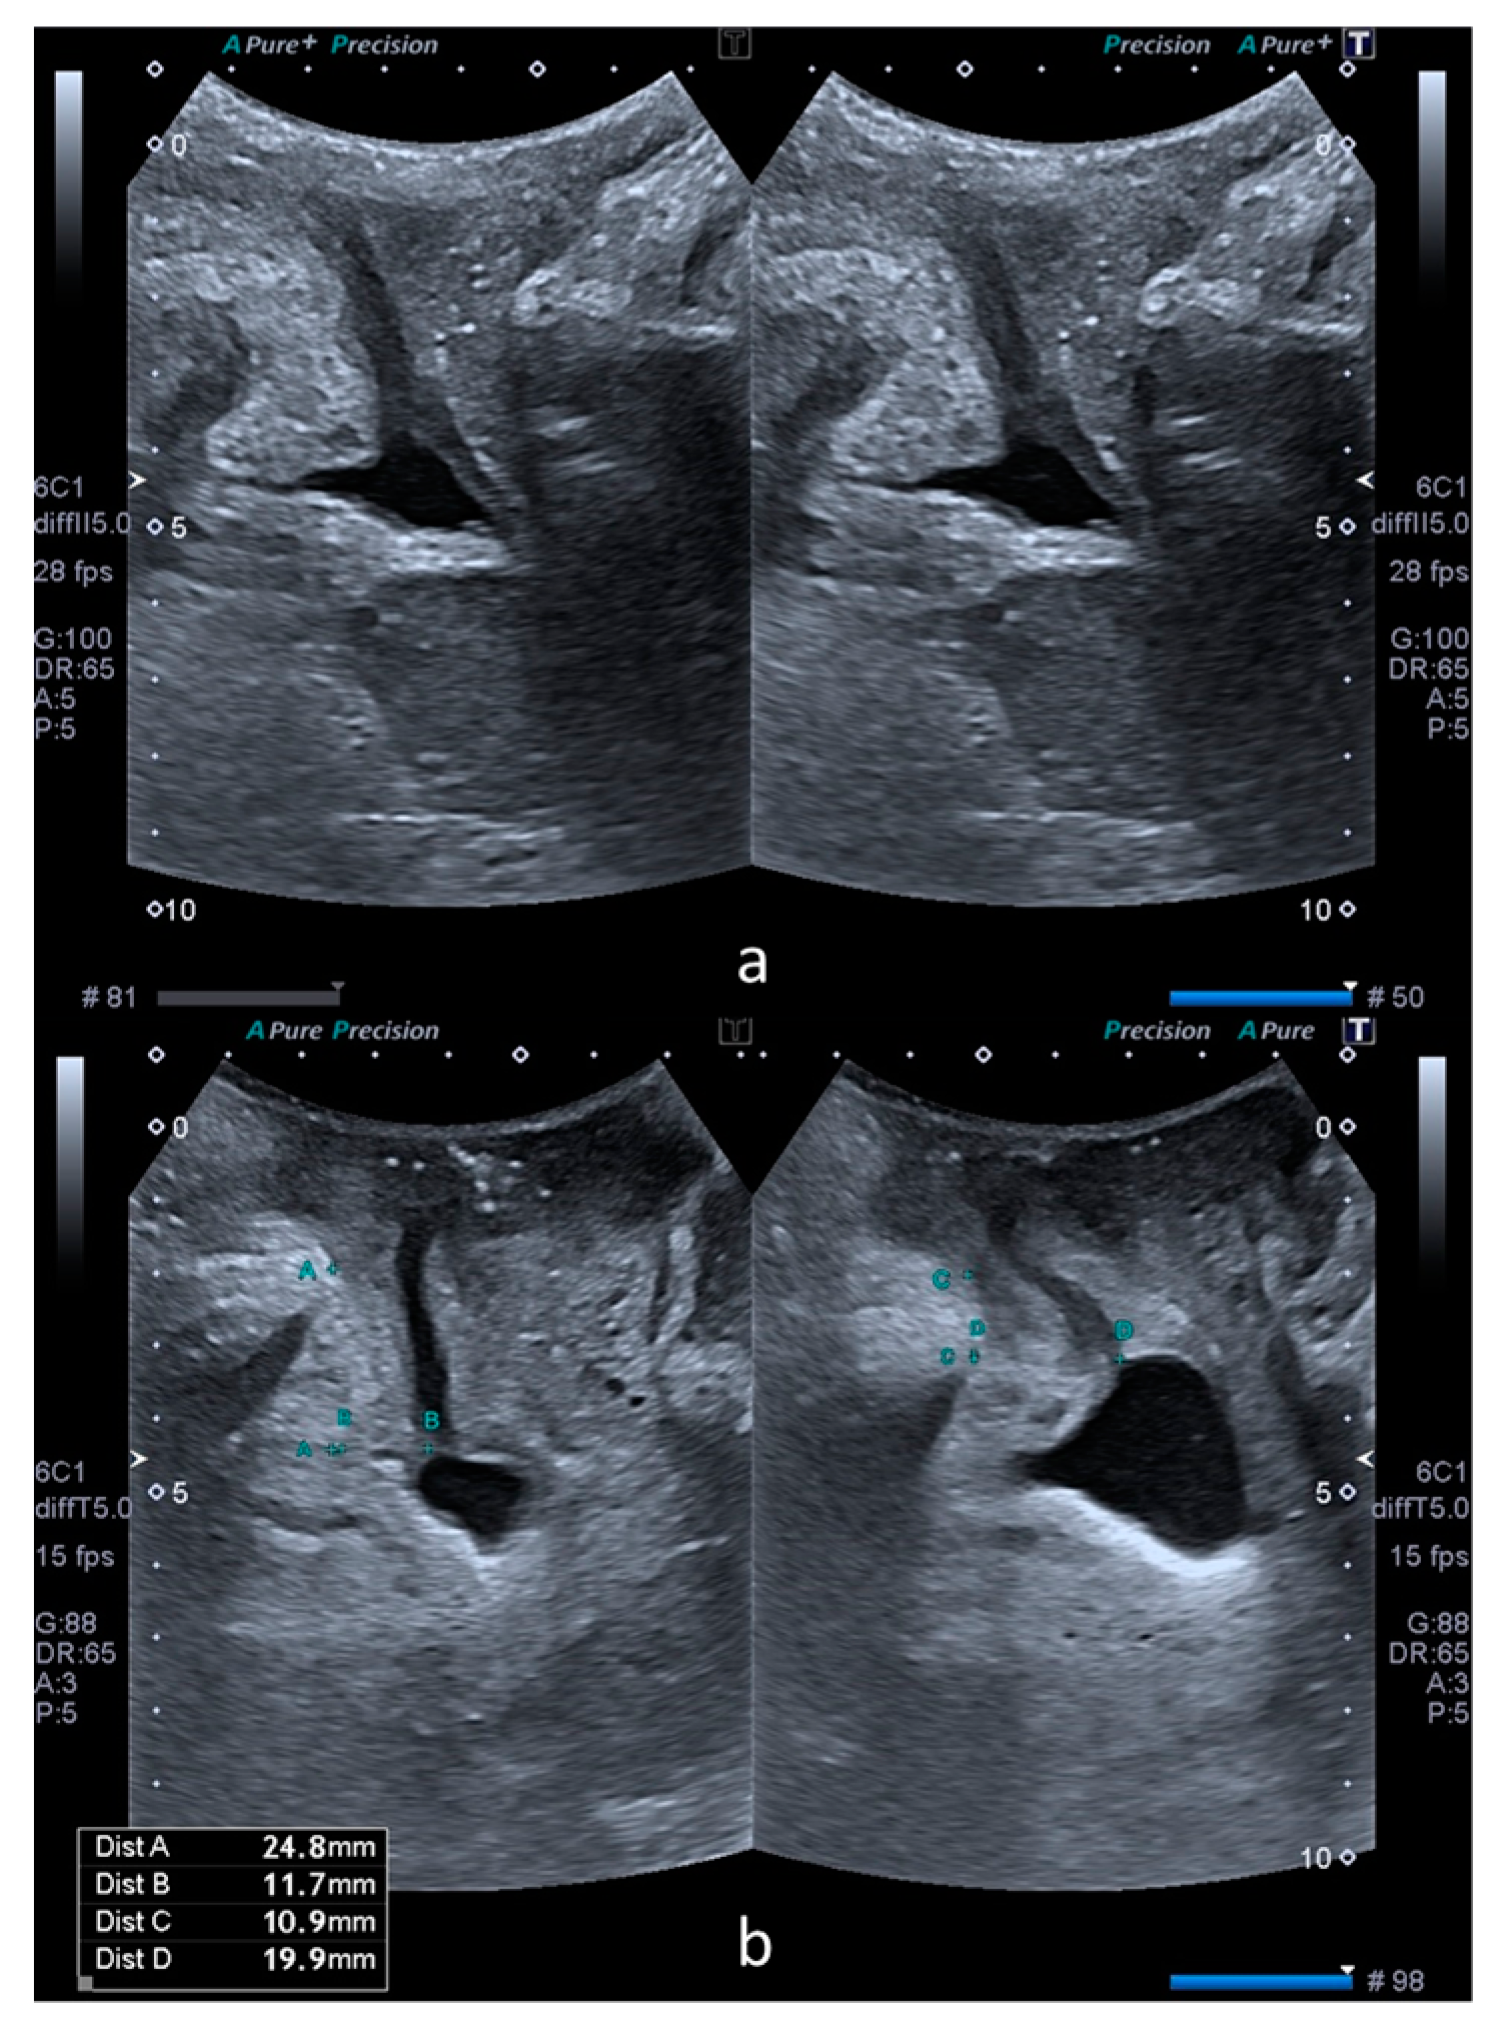

The bladder neck mobility was quantified by subtracting SPBN and DLM values at rest and on Valsalva, with the results being noted as ΔSPBN and ΔDLM. Subsequently, the rest, Valsalva and subtraction values of SPBN and DLM were compared between the cystocele and control groups. Figure 1 illustrates these parameters in a patient from the control group (a) and another patient from the case group (b).

Figure 1.

Comparative transperineal US images at rest (left) and on Valsalva maneuver (right). Image (a) was obtained from a patient without a cystocele. Image (b) was obtained from a patient with a cystocele. Image b also shows the measurements performed in the XY coordinate system. Dist A (left) and dist C (right) correspond to SPBN and dist B (left) and dist D (right) correspond to DLM.